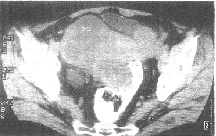

图1 浆液性乳头状囊腺癌 CT扫描示盆腹腔内巨大不规则形囊实性肿块,大小为15cm×11cm×10cm,囊性部分CT值为10~22Hu,实性部分CT值为35~45Hu,壁结节CT值为34.8Hu 图2 低分化浆液性囊腺瘤 CT平扫示右侧卵巢不规则形囊实性肿